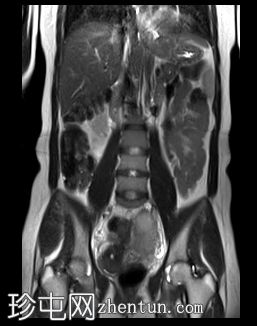

冠状位

T2快速加权像

6.jpg

双侧卵巢向内侧移位,形成“接吻卵巢征”。

子宫后壁子宫圆锥增厚,累及直肠前壁。

子宫圆韧带增厚。

子宫、双侧卵巢和直肠因挛缩性粘连/纤维带而靠近,形成近期描述的深部盆腔子宫内膜异位症的“三叶草征”。

深部盆腔子宫内膜异位囊肿和双侧卵巢子宫内膜异位囊肿的检查结果令人印象深刻。